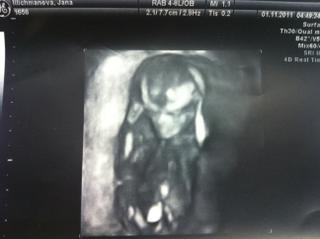

Miminko je krásně vidět - to je 3D fotečka, viď? To už se dělá i takto brzy? Mě v Gennetu říkali od 24.tt, tak uvažuji, že se na to pomalu objednám. A už vám řekli i pohlaví?

tuhle fotku nám dali minulý týden na screeningu, je to 4D, promítají to na zeď, takže to bylo moc krásné, dokonce Dr. říkal, že je mimi zatím celý tatínek🙂tak se ten můj chlap dmul jak kohout a pak se slavnostně rozbrečel 😀

Já jsem právě byla překvapená, že na konci třetího měsíce už to takhle jde..Pohlaví nevím, protože mimi vůbec nespolupracovalo a pořád tam předvádělo své akrobatické kousky a dokotor říkal, že prý budem rádi, když se to dovíme v 9. měsící, jestli bude v tom řádění pokračovat i při dalších kontrolách🙂

@ma.ja Je krásná, musíš být neskonale šťastná 🙂